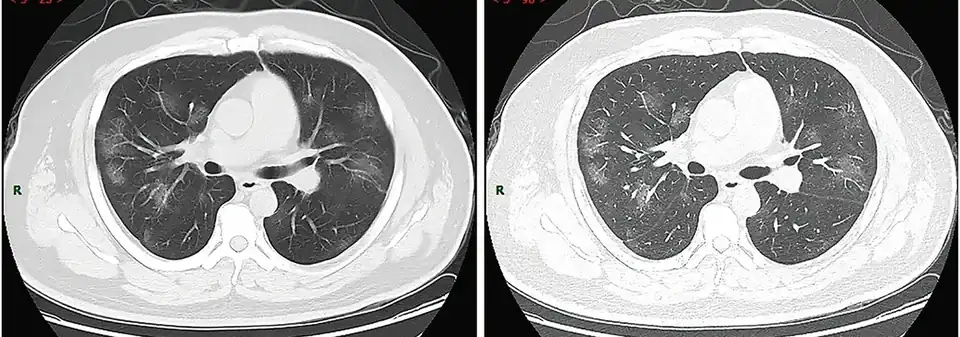

* 14. april 2020 : (PDF-fil) "Information om PCR test for COVID-19 til almen praksis" Arkiveret 18. april 2020 hos Wayback Machine - ↑ Billedbeskrivelse på Commons : "Typical CT imaging manifestation (case 1). A 38 years old male with fever without obvious inducement (39.3 ℃), dry cough and shortness of breath for 3 days. Laboratory test: normal white blood cells (6.35 × 109/L), decreased lymphocytes percentage (4.1%), decreased lymphocytes count (0.31 × 109/L), decreased eosinophil count (0 × 109/L)), increased C-reaction protein (170.91 mg/L), increased procalcitonin (0.45 ng/ml). Imaging examination: multiple patches, grid-like lobule and thickening of interlobular septa, typical "paving stone–like" signs. a SL(Slice): 6 mm; b high-resolution computed tomography(HRCT). HRCT. high-resolution computed tomography"